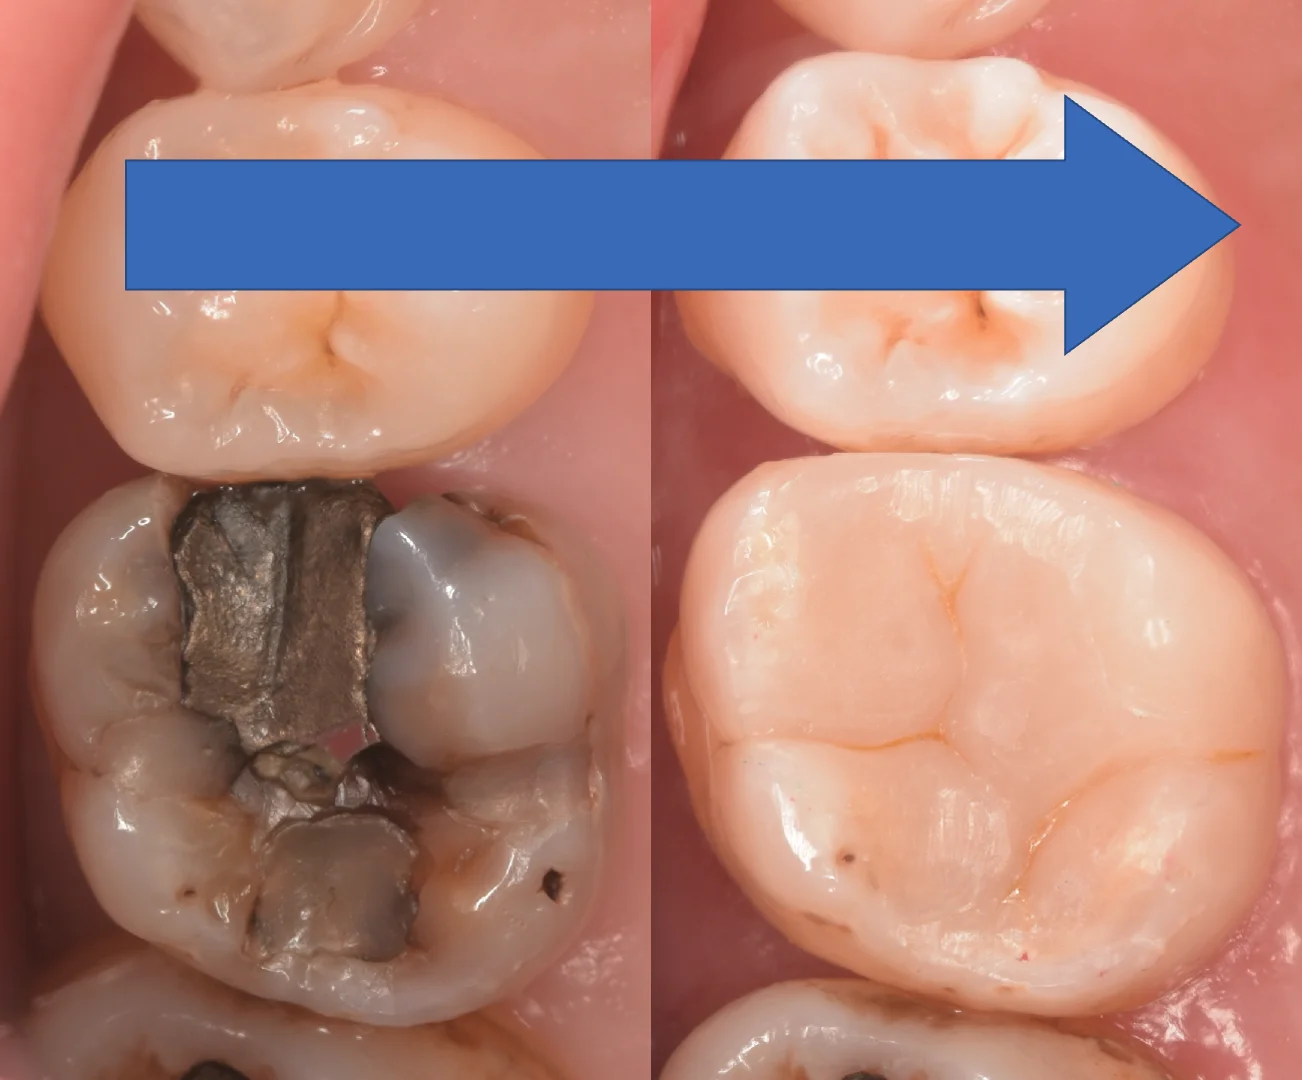

術前術後です。

今回のケースは本来であればダイレクトボンディングではなくセラミックなどのクラウンによる修復が最も無難ではありますが・・・

患者が歯科医師であること、咬合を含め、力のコントロールに問題がないことからダイレクトボンディングでも長期予後を期待できると患者さん本人と相談して行なっていきました。

今後もし欠けたりしたら型取りすると思います。

一般の方の場合はここまでのサイズの虫歯は初手から被せ物で行いますので、十分にご注意ください。